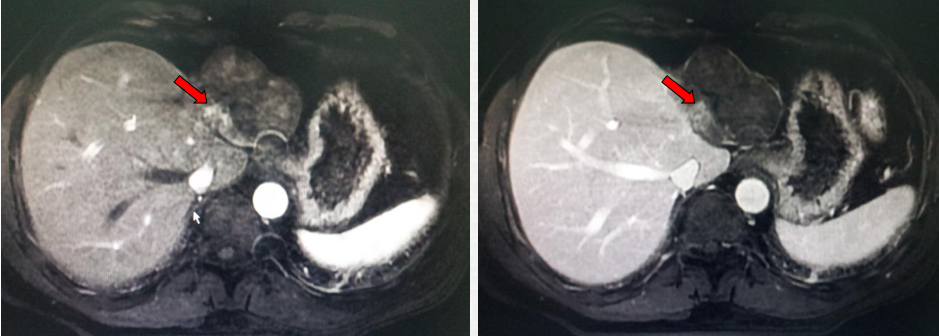

2011-02-12复查CT示:肝左叶碘油散在沉积,病灶大部分仍有活性,肝右后叶病灶未见碘油沉积;门静脉癌栓较前进展,累及主干及右支;肝左静脉及下腔静脉内癌栓无明显变化。AFP:26802 ng/ml。

2011-04-20复查CT示:肝左叶病灶较前缩小,肝右叶病灶见碘油致密沉积;门脉癌栓左支较前缩小,右支癌栓消失;下腔静脉、肝左静脉癌栓消失。AFP:4983 ng/ml。

2011-06-09(第二次TACE后4个月)复查肝脏CT示:肝左叶病灶继续缩小,但仍有肿瘤残留。AFP:8137 ng/ml(较上次复查明显升高)。

2011-08-15复查CT示:肝左叶病灶大小较前相仿,仍有肿瘤残留。

2011-08-22(第3次TACE后2个月) 行CT引导下微波消融+无水酒精固化术

2013-07-17复查上腹部MRI:肿瘤边缘出现复发病灶。

2013-07-22 对复发病灶再次行微波消融治疗